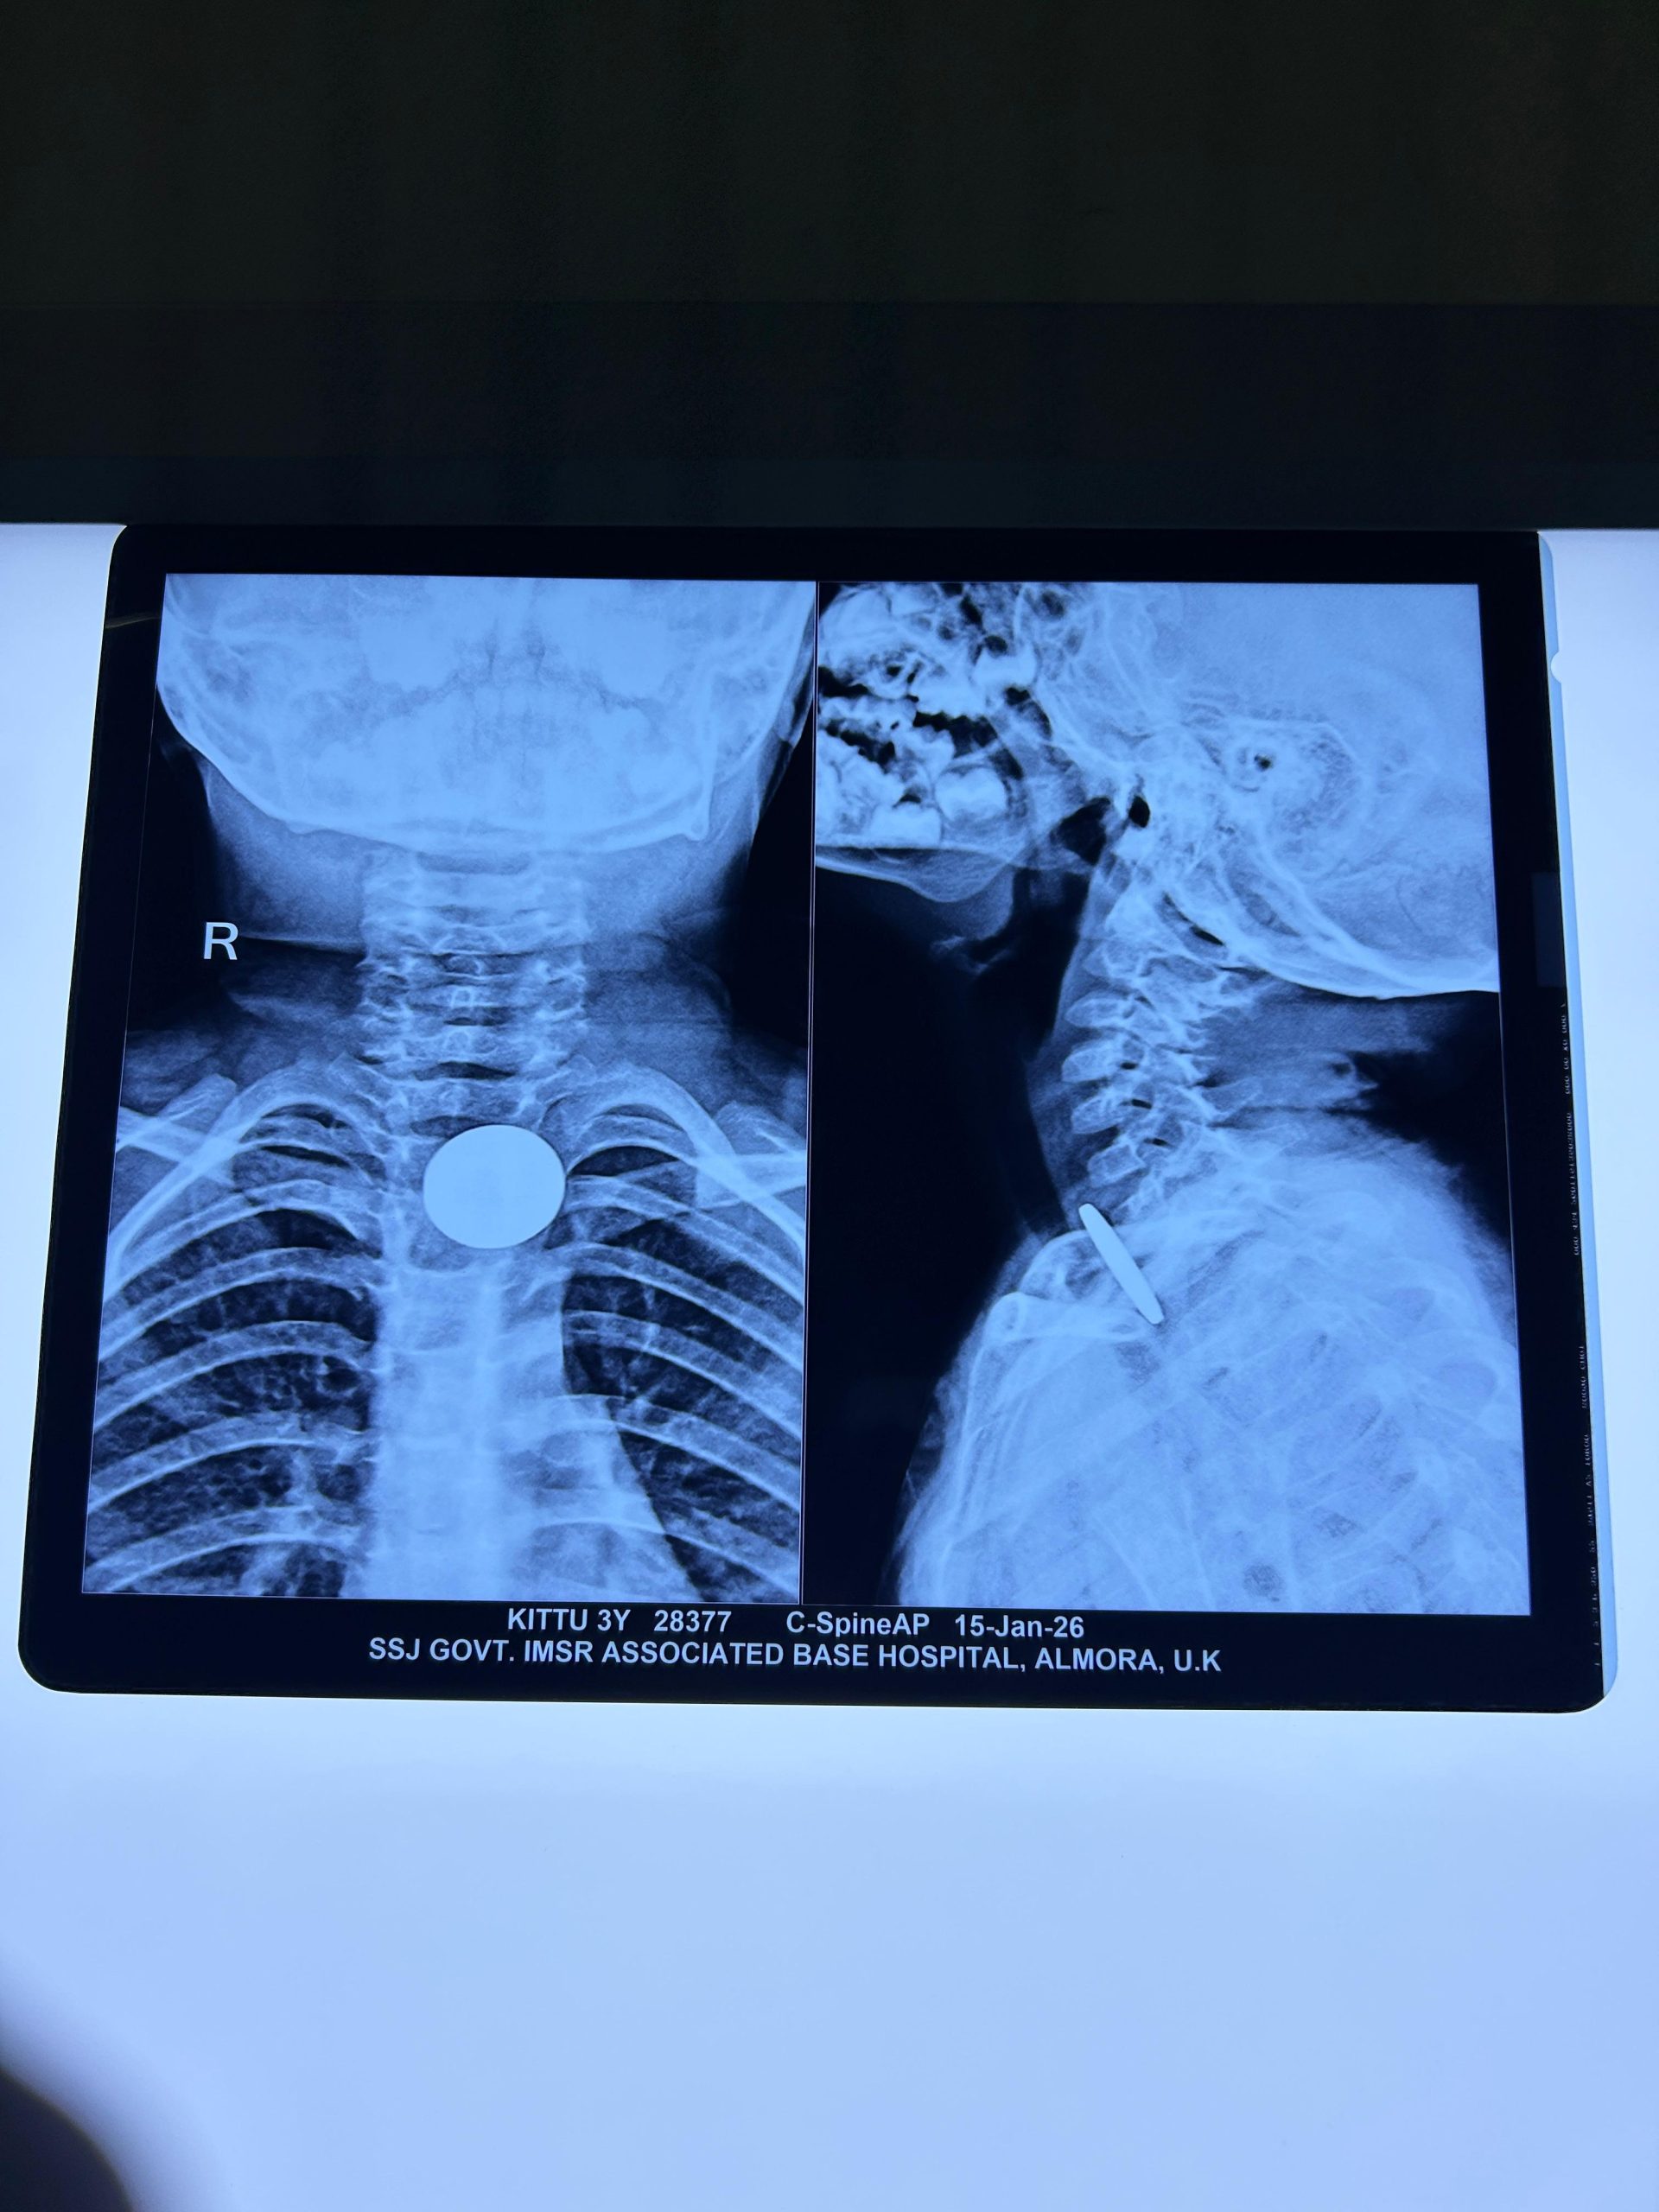

Aolmora-कल रात सोमेश्वर में एक 3 वर्षीय बच्ची ने एक सिक्का निगल लिया। संध्या आयु/लिंग: 3 वर्ष / महिला पिता का नाम: मोहन राम निवासी:सोमेश्वर । आज उन्हें सोमेश्वर CHC (सामुदायिक स्वास्थ्य केंद्र) से राजकीय मैडीकल कालेज अल्मोड़ा रेफर किया गया। यहाँ आने पर गले (Neck) का एक्स-रे फिर से किया गया, जिसमें सिक्का क्रिकोफैरिनक्स (Cricopharynx) के पास फंसा हुआ पाया गया।

मरीज को बेहोश कर नली (Intubation) डाली गई और ईसोफैगोस्कोपी (Oesophagoscopy) की प्रक्रिया के माध्यम से सिक्के को सुरक्षित रूप से बाहर निकाल लिया गया। ट्यूब निकालने (Extubation) के बाद मरीज की स्थिति संतोषजनक पाई गई और उन्हें पोस्ट-ऑपरेटिव वार्ड (Post-op) में शिफ्ट कर दिया गया है।